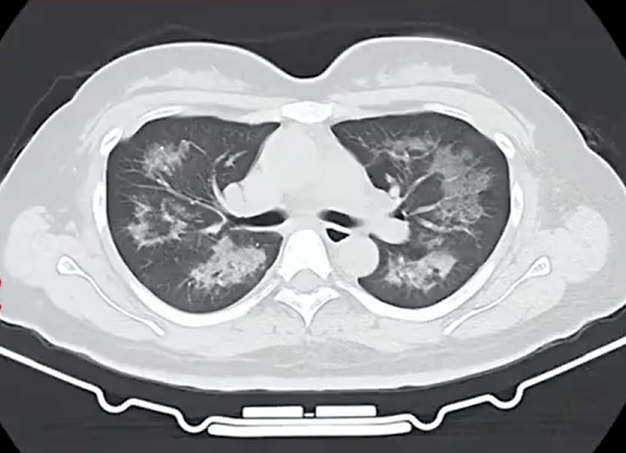

胸部CT进一步显示,她的双肺出现多发斑片状模糊影,被诊断为间质性肺炎。医生判断,病因很可能与她近期长期接触的某类物质相关。经过反复细致地询问病史,小江才说出自己长期、频繁使用定妆喷雾的习惯。